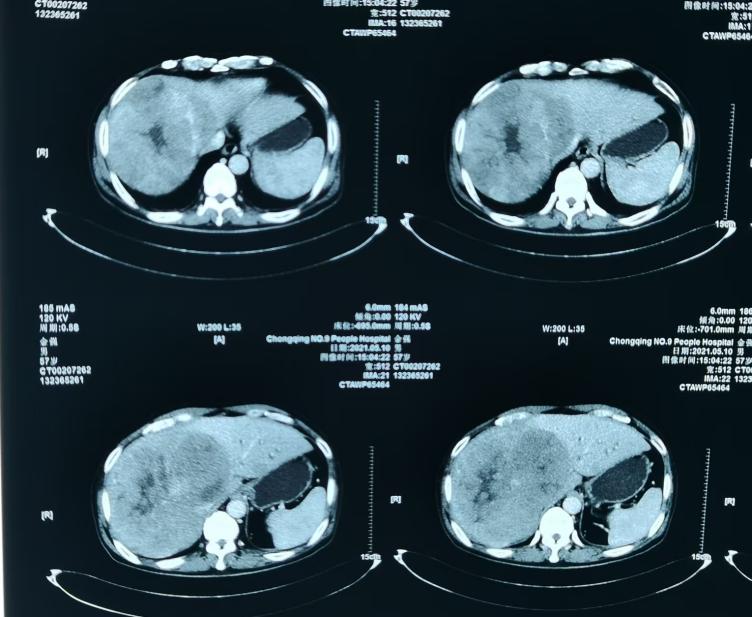

62岁男性患者,父亲有胰腺癌史。2021年5月发现消瘦(80 kg→65 kg),于外院CT检查显示右肝HCC占位(12.9×17.4 cm ),右肺下叶背段肺动脉栓塞。2021年5月13日到我院就诊入院,检测示乙肝表面抗原(HBsAg)<0.05 IU/mL,谷丙转氨酶(ALT)116 IU/L,甲胎蛋白(AFP)571.6 ng/mL,异常凝血酶原(APT)158 890 mAU/mL,2021年5月19日行肝脏MRI检查显示肝内多发占位,考虑肿瘤性病变(巨块型肝癌)伴肝内转移,门静脉癌栓,局部肿瘤内出血。

治疗前肝脏MRI影像

注:2021年5月19日肝脏MRI影像,提示巨块型肝癌,伴肝内转移,门静脉癌栓,局部肿瘤内出血。